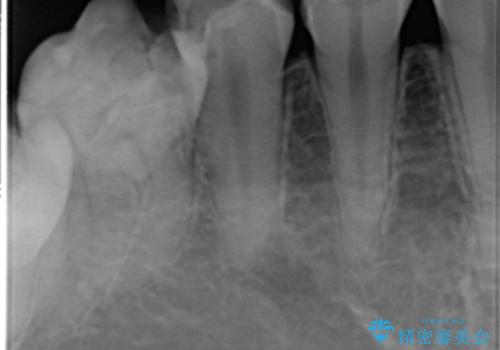

下顎の埋伏していた親知らずも抜去しました。